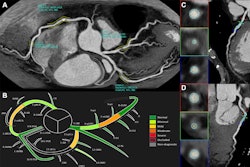

72-year-old female participant with heart failure. Patient underwent coronary CTA by photon-counting detector CTA, acquired in UHR mode. Agatston score was 1,615. Heart rate was 59 beats/min. (A) Reconstructed UHRnormal image. Proximal RCA shows calcified plaque. Inset shows cross-section of RCA at level of thin line traversing vessel. (B) Reconstructed UHRthin image. Proximal LCX shows calcified plaque. Inset shows cross-section of RCA at level of thin line traversing vessel. Insets show less blooming artifact from calcified plaque for UHRthin than for UHRnormal. Stenosis at site of calcification was measured as 60% for UHRnormal and 30% for UHRthin. (C) Image from subsequent invasive coronary angiography shows 30% stenosis of RCA (arrow). UHR = ultrahigh resolution. Images and caption courtesy of the AJR.